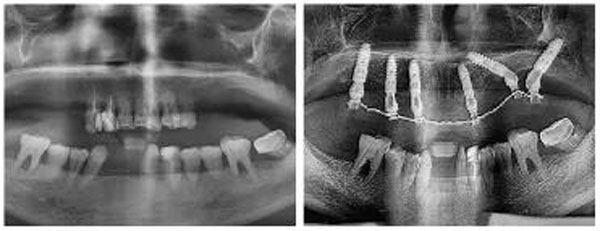

经过全面的检查和细致的沟通,新桥光华店种牙团队为邓女士量身定制了半口即拔即种-即刻负重修复方案,通过在上颌种植6颗植体,即可恢复12颗牙齿的咀嚼功能。面对超出预期的治疗费用,夫妻俩断然拿出了自己房子的部分装修款。而这样坚决的原因,余先生用自己潇洒的人生态度做了最好的注解。

邓女士种牙前后全景片对比